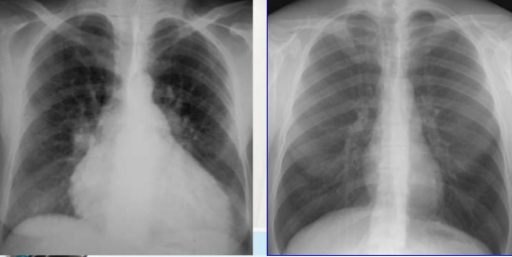

Để xác định bóng tim to trên phim chụp X-quang cần xác định tỷ lệ tim ngực, chỉ số tim ngực là tỷ lệ giữa kích thước chiều ngang của bóng tim và kích thước chiều ngang lồng ngực. Bóng tim bình thường trên phim chụp tim phổi thẳng có tỷ lệ tim ngực là từ 0,5-0,55. Bóng tim to khi tỷ lệ tim ngực lớn hơn 0,55.

Khi lồng ngực kéo dài, tim ở trạng thái treo. Lúc đó trục của tim gần như song song với trục đứng của cơ thể, người ta gọi là tim hình giọt nước, đường kính tim giảm rõ rệt. Tình trạng bóng tim nhỏ có thể gặp trong các bệnh lý như:

- Bệnh khí phế thũng gây ra do sự mất chức năng của các túi phế nang và các tiểu phế quản do căng giãn quá mức hoặc bị phá hủy do quá trình viêm mạn tính. Tình trạng này kéo dài làm mất tính đàn hồi của hệ thống hô hấp, sau khi hít vào bệnh nhân bị khó thở ở thì thở ra nên không khí bị ứ lại tại phổi hình thành nên các túi khí chứa không khí nghèo oxy. Trên phim chụp X-quang điển hình là hình phổi ứ khí và bóng tim nhỏ hình giọt nước.

- Bệnh phổi mạn tính, hen phế quản: Tình trạng này làm cho khí bị ứ tại phổi nên phim chụp X-quang lồng ngực rộng dạng hình thùng, bóng tim nhỏ.